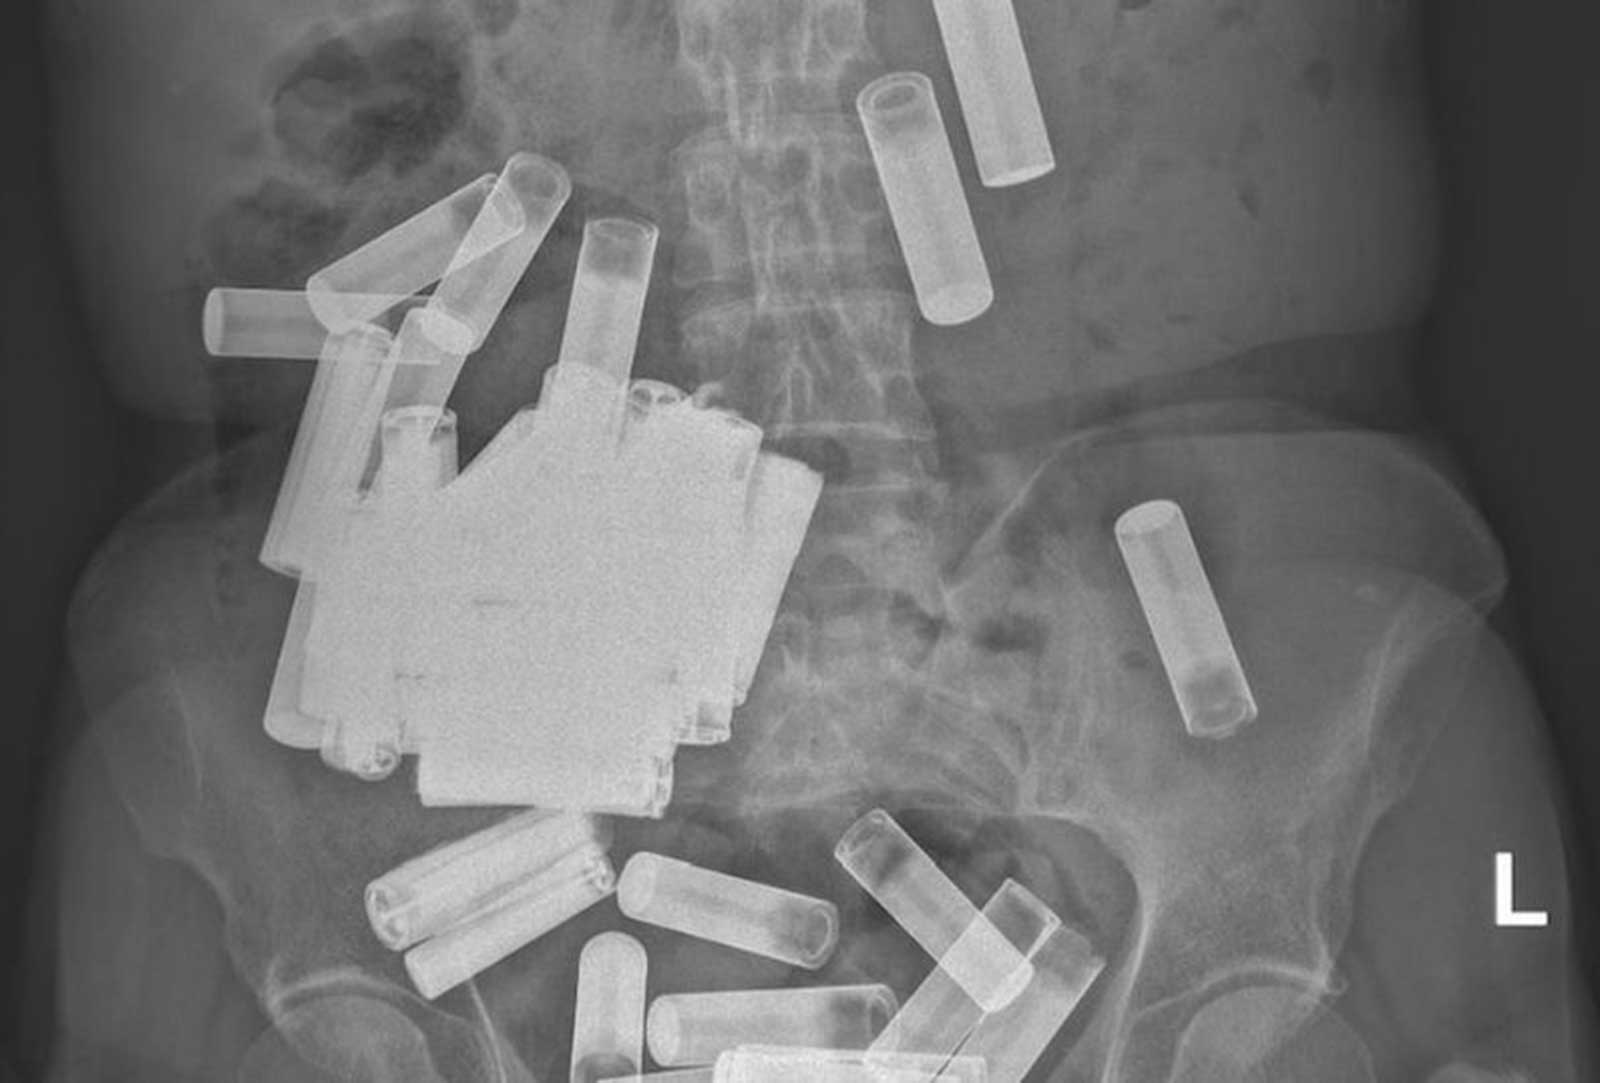

نجح أطباء في مستشفى جامعة سانت فنسنت بالعاصمة الأيرلندية دبلن، في إنقاذ حياة امرأة ابتلعت 55 بطارية. وكشف الأطباء، أن السيدة العجوز دخلت إلى المستشفى بحالة حرجة إثر قيامها بهذا التصرف الغريب وغير المبرَّر، حسبما نقل عن صحيفة «ساينس أليرت» العلمية. وأوضحوا أنه بمجرد إجراء الأشعة السينية على جسدها تبين وجود 55 بطارية AA وAAA في بطنها وقولونها. ولفتوا إلى أن المرأة أصيبت بتقلصات في المعدة وانتفاخ بسبب وزن البطاريات التي ابتلعتها.

وأجرى الأطباء للسيدة عملية جراحية لانتشال 46 بطارية، بعدما طرد جسمها 5 بطاريات، وسحبوا 4 أخرى من القولون. وأكدوا أنها ستعود لممارسة حياتها بصورة طبيعية، إذ إن ابتلاعها للبطاريات لم يؤثر في جهازها الهضمي، مشيرين إلى عدم علمهم بالسبب الذي دفعها إلى الإقدام على ذلك. وأشاروا إلى أن ابتلاع البطاريات خطير ويمكن أن يسبب مشكلات كبرى، أهمها، إصابة الغشاء المخاطي، والانثقاب بالجسد.